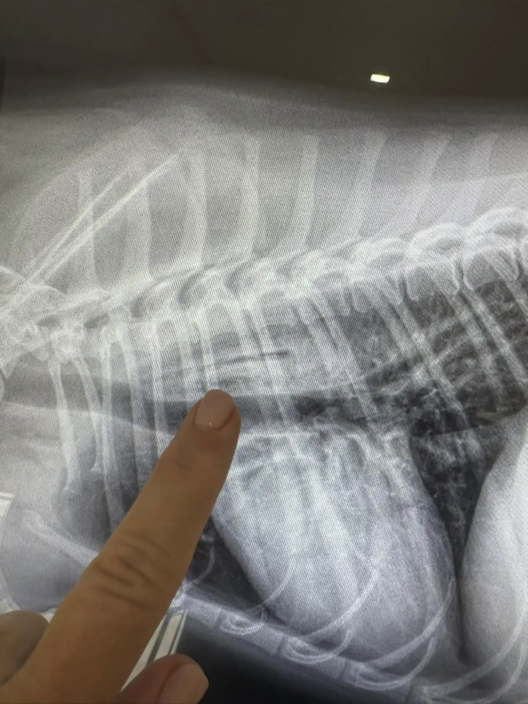

But nothing had shown up in the original scans. The rescue ordered a barium study and sent the images to a specialist — and that’s when they finally saw it.

“You could barely make it out,” McKnight said. “But there it was — a mango seed, lodged horizontally in her throat.”

It explained everything: the pain, the retching, the steady decline. Luna needed emergency endoscopic surgery immediately. Her chances of surviving were slim.